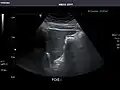

Left kidney -